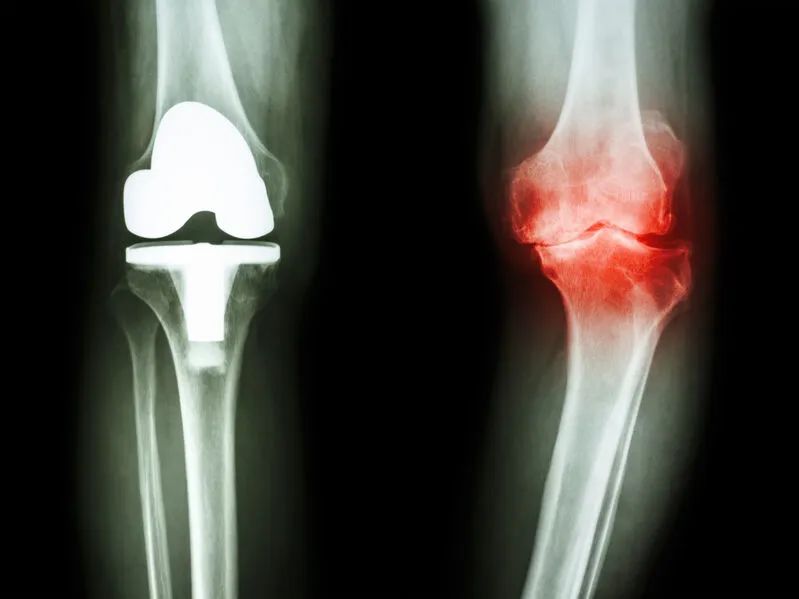

骨关节炎目前仍没有明确有效的治愈措施,目前的治疗方法主要以止痛对症治疗和延缓骨关节炎进展的治疗为主,对于晚期骨关节炎患者,膝关节表面置换是目前唯一有效的治疗手段。国际上通用的骨关节炎治疗主要采用阶梯式治疗方法。

晚期骨关节炎患者

目前认为唯一有效的治疗方法为膝关节置换手术,包括单髁置换、全膝关节表面置换等手术方式。

单髁置换主要针对单纯的内侧腔室出现软骨磨损,而其它部位软骨正常的患者,对于全膝关节出现软骨磨损,可考虑行全膝关节表面置换手术。